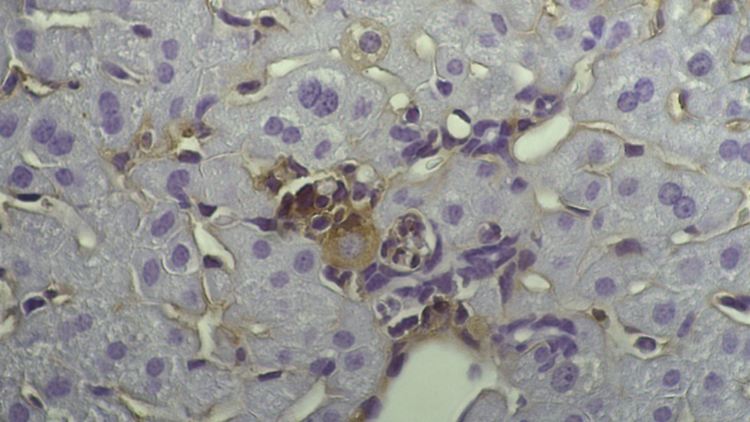

Für unheilbar Kranke gibt es Hoffnung durch genetisch veränderte Viren.

(Foto: picture alliance / dpa)